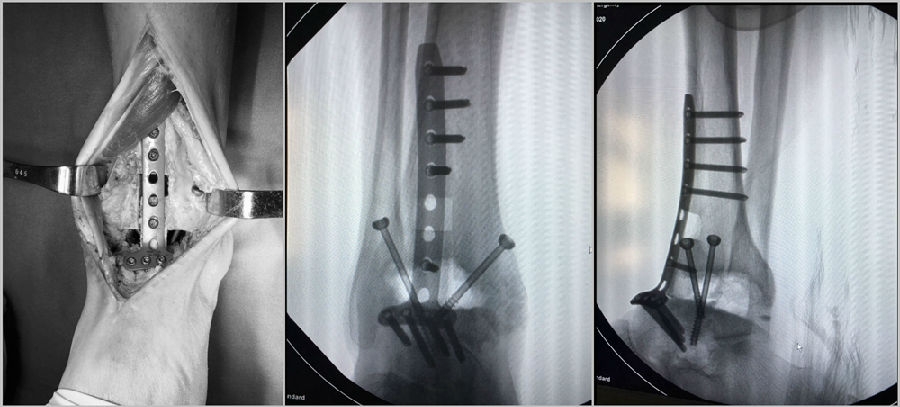

病例报告之一,切口显露同前。

固定方法:

病例报告之二,xx,男,56岁,左踝创伤性关节炎。左踝崴伤6年,疼痛加剧3年。切口显露同前。

手术前资料

手术中资料

图23 手术后资料